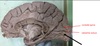

3

1. Identify 3 2. Identify 4 3. Identify 5 4. Identify 6 5. Identify 7 6. Identify 8 7. Identify 9 8. Identify 10 9. Identify 11 10. Identify 12

1. Dura Mater 2. Falx cerebri 3. Corpus callosum 4. Septum Pellucidum 5. Fornix (hippo to mamillary bodies) 6. Interthalmic adhesion 7. midbrain 8. Straight sinus 9. internal carotid 10. Tentorium cerebelli

4

1. Name the dural venous sinuses related to 4 2. Name the dural venous sinuses related to 12 3. How does 10 terminate

1. superior and inferior saggital, straight sinus 2. sigmoid, Transverse and superior petrosal sinuses 3. Great Vein of Galen